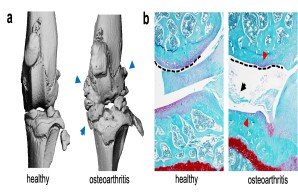

Molecular biology analysis of post-traumatic osteoarthritis

Joint injury is a common cause of post-traumatic joint degeneration (osteoarthritis). Apart from symptomatic treatments, currently only artificial joint replacement is available for the treatment of advanced osteoarthritis. In our research group, we are therefore investigating the pathophysiology of post-traumatic osteoarthritis using state-of-the-art experimental methods in order to develop new treatment strategies for affected patients in the long term.

Fig.: Radiological (µCT; a) and histological (b) imaging of joint changes in post-traumatic osteoarthritis. The classic signs of osteoarthritis appear with osteophytes (blue arrows), meniscal degeneration (black arrow), joint deformation (dashed line), and loss of articular cartilage (red arrows).